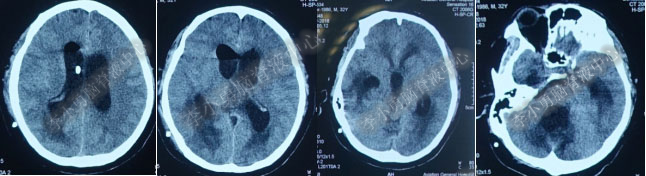

2017年6月27日(分流术后5天),复查头部CT(图-6)显示幕上脑室及第四脑室均有所缩小。

图-6:2017年6月27日头部CT

图-7:2017年7月30日头部CT

图-8:2017年9月18日头部CT